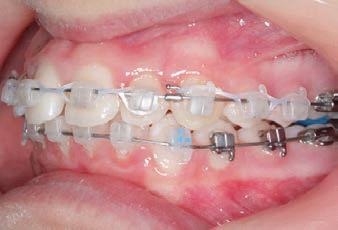

CLASS II DIV.1 - Marra

INITIAL - 4/4/18

PROGRESS 1 - 26/9/18 - Class I platform accomplished in 5.75 months with Motion 3D COLOR Appliance

PROGRESS 2 - 26/9/18 - Placement of the SLX 3D Clear Brackets

with M-ONE .015 Cu Nitanium 27°

PROVIDED BY: DR. LUIS

PROGRESS 3 - 30/10/18 - With M-TWO .020 x .020 Cu Nitanium 35° archwire

PROGRESS 4 - 27/11/18 - 3 links power chain: 5, 4, bypass 3 to crimp hooks

PROGRESS 5 - 13/3/19 - With M-TWO .020 x .020 Cu Nitanium 35° archwire

PROGRESS 6 - 1/8/19 - With M-THREE.019 x .025 Beta Titanium wire